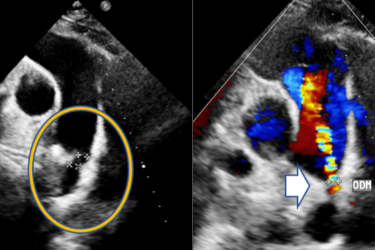

Tại Bệnh viện Hoàn Mỹ Cửu Long, bệnh nhi được bác sĩ chỉ định thực hiện siêu âm tim Doppler, các bác sĩ xác định bệnh nhi bị thông liên nhĩ với kích thước lỗ thông có thể xử trí bằng phương pháp can thiệp bít dù qua da, đây là một thủ thuật ít xâm lấn giúp đóng lại lỗ thông liên nhĩ mà không cần mở ngực.

Ê-kíp Khoa Nội Tim mạch - Can thiệp nội mạch đã tiến hành thủ thuật bít hoàn toàn lỗ thông liên nhĩ cho bé T. trong khoảng 45 phút. Như vậy, bé không cần phải thực hiện phẫu thuật tim hở. Sau thủ thuật, sức khỏe bệnh nhi ổn định, hồi phục nhanh và đã được cho ra viện tái khám ngoại trú sau 24 giờ.